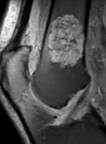

Chondroid Tumor

Chondroid Bone Tumor Detection

Automatic chondroid bone tumor detection using deep learning.

Chondroid Machine

Adapted Stanford Bone Bayes engine to discriminate benign vs malignant chondroid bone tumors.

Bone Tumor Precision

Precision Diagnosis of Bone Tumors

Using deep learning and bayesian network for generating ddx of bone tumors on xray.